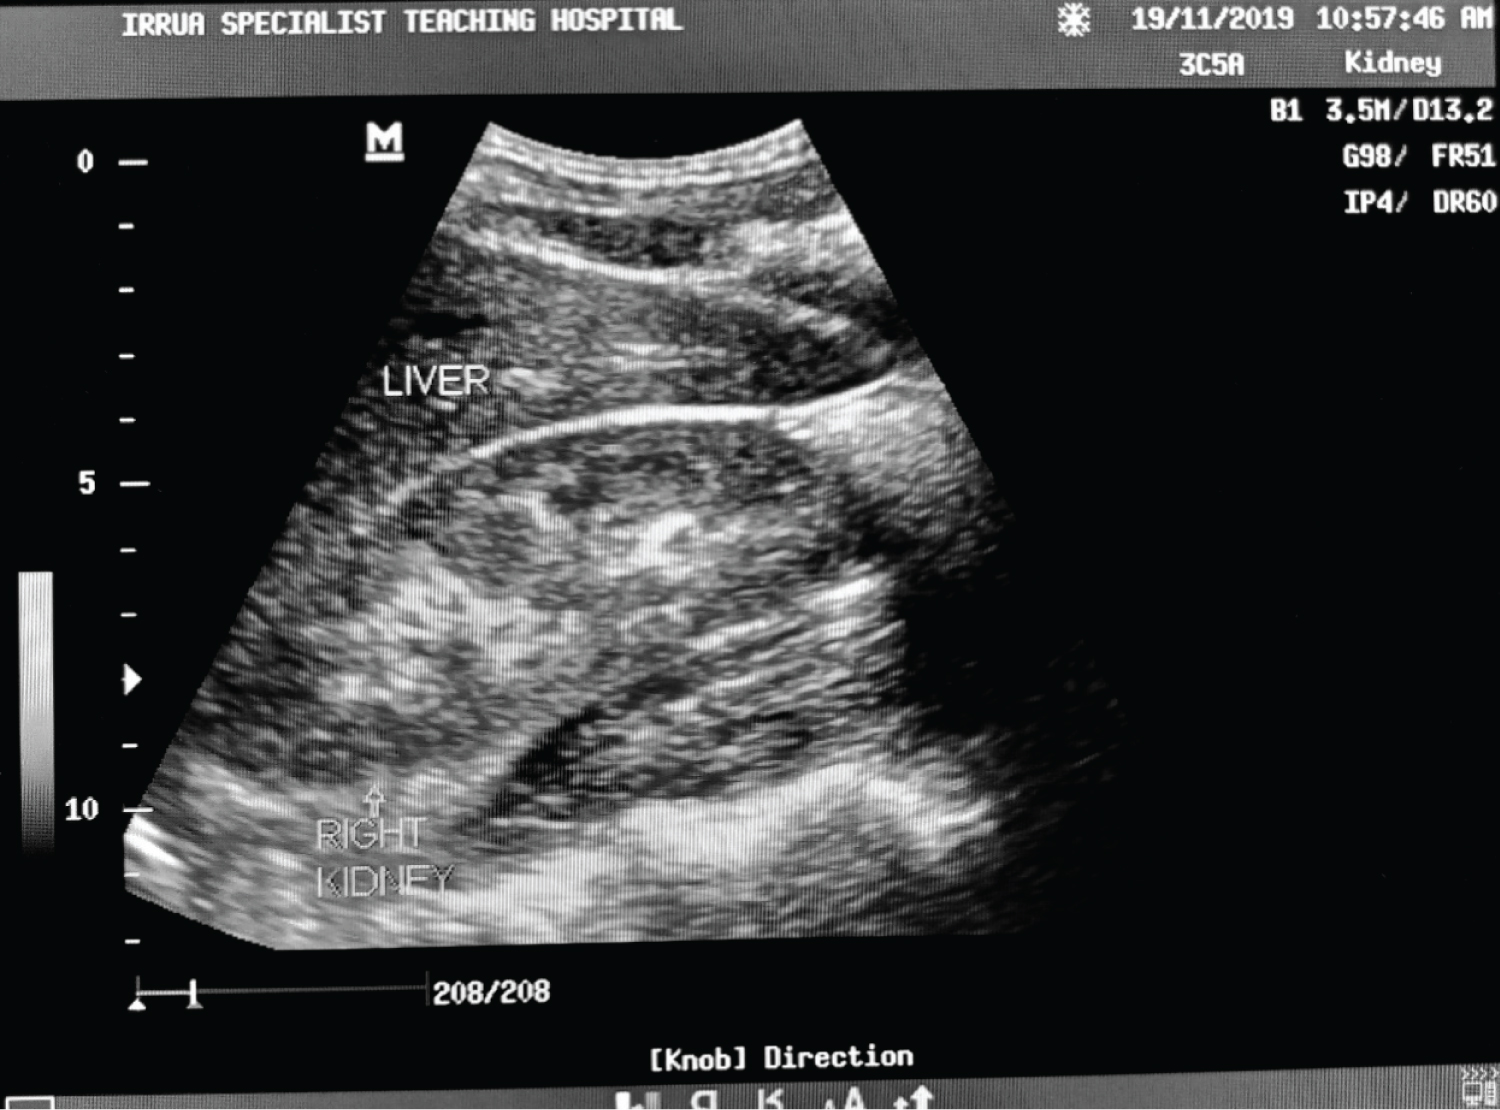

Figure 4: Ultrasound of abdomen showing a longitudinal section of the right kidney with its echogenicity lower than that of the liver (Grade 0 renal cortical echogenicity). Serum creatinine level of 1.0 mg/dl. View Figure 4

Figure 5: Ultrasound of the abdomen showing longitudinal sections of the right kidney with its echogenicity equal to that of the liver and maintained cortical-medullary differentiation (grade 1 echogenicity) in a Lassa fever patient with serum creatinine level of 1.5 mg/dl. View Figure 5